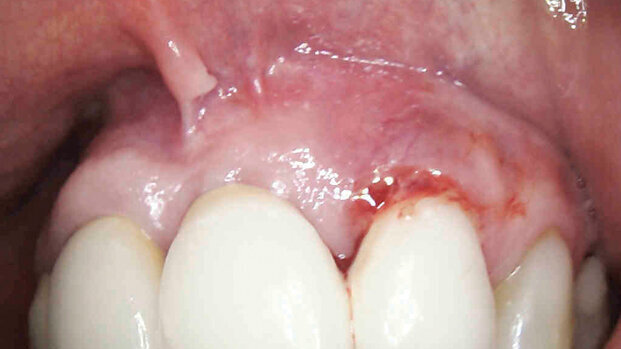

Il presente lavoro descrive la procedura con laser neodimio Nd:YAG 1064 nm per intervento di perimplantite.

La paziente, di sesso femminile di 78 anni, riferisce fastidio sulle gengive dei centrali superiori e presenza di sangue sullo spazzolino.

Pregresso ictus in terapia con anticoagulanti (cumadin), non beve e non fuma.

All’età di 37 anni, causa incidente automobilistico, ha riportato l’avulsione traumatica dell’elemento 2.1 e frattura dell’elemento 1.1 e 2.2. Il caso clinico fu risolto con un impianto dell’elemento 2.1 e terapia endodontica dell’1.1 e 2.2 e un ponte di tre elementi tra 1.1 e 2.2. A distanza di diversi anni, circa 5 anni fa, il vecchio manufatto protesico è stato sostituito.

Presenza di un ponte sugli elementi 1.1, 2.1, 2.2 il tessuto molle è edematoso, l’esame generale del cavo orale dei tessuti molli e della lingua non presentano anomalie. L’esame parodontale quantifica una sacca di circa 9 mm sia palatalmente sia vestibolarmente sugli elementi 2.1 e 2.2 e una sacca di 5 mm sull’elemento 2.1; è presente sanguinamento e nessuna mobilità del ponte.